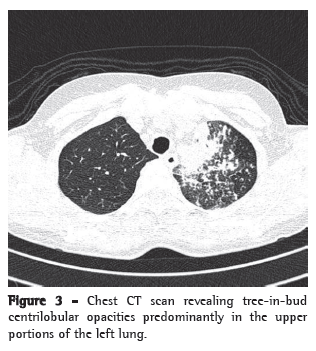

We report the case of a 41-year-old female homemaker from the city of Piracanjuba, located in the state of Goiás, Brazil. The patient had previously been diagnosed with arterial hypertension and had been using enalapril for several years. In addition, she had been diagnosed with RA more than ten years prior. During that period, she was treated with various therapeutic regimens for RA. She had been under treatment prednisone (5 mg/day) and methotrexate. Since she continued to have many joint symptoms, adalimumab was also prescribed. After two months of adalimumab treatment, the patient began to have low fever almost daily, as well as mild dry cough and mild asthenia. She sought medical attention at an emergency room in the city of Goiânia, also located in the state of Goiás, and was diagnosed with pneumonia after a chest X-ray (Figure 1). The patient used azithromycin (500 mg) for five days, in accordance with a prescription. The patient initially presented a slight improvement, but the dry cough and fever returned after the medication was discontinued. Two months later, since her clinical profile remained the same, she sought medical attention again, at which point a ten-day course of levofloxacin (500 mg/day) was prescribed. Again, she presented a slight improvement but the symptoms reappeared after the end of the course.

The patient stated that she was not a smoker or an alcoholic. She reported that she had tested negative on a tuberculin skin test (TST) conducted before the initiation of adalimumab treatment, and that, according to the rheumatologist who treated her, a chest X-ray performed at the time was normal. After the use of azithromycin (three and half months prior), she also received an additional infusion of adalimumab. Physical examination revealed mild pallor and no palpable lymph node enlargement. There were fine rales in the upper third of the left hemithorax and coarse rales in the middle third of the right hemithorax, as well as scattered rhonchi. Her hands and feet had joint deformities. A chest X-ray revealed alveolar opacities in the left upper lobe, left lower lobe and middle lobe, as well as images suggestive of bronchogenic dissemination (Figure 2). A CT scan of the chest revealed tree-in-bud centrilobular opacities (Figure 3).